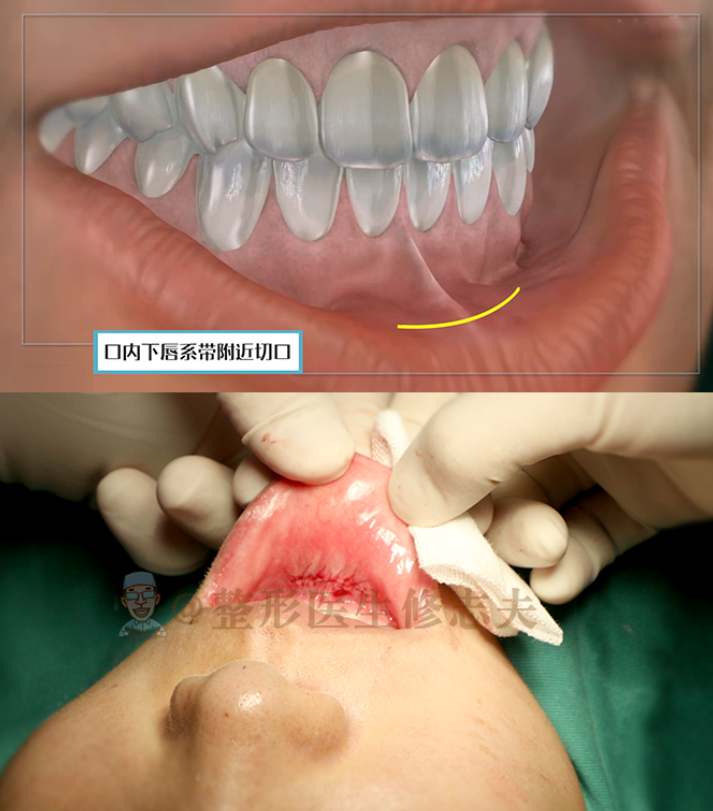

假体隆下巴的切口主要有两个,一个是在下巴下方的外切口,一个是在口内下唇系带附近的内切口。

▼假体隆下巴的两种切口

假体隆下巴一般会选择口内切口,这样外观看不来;术后肿胀反应也轻,加上医生会用胶布包扎定型,也会加速消肿,所以肿胀并不。